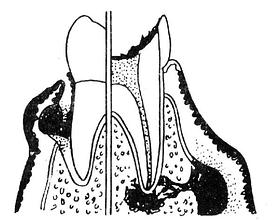

牙周袋形成:由于炎症的扩展,牙周膜被破坏,牙槽骨逐渐吸收,牙龈与牙根分离,使龈沟加深而形成牙周袋。可用探针测牙周袋深度。X线检查时可发现牙槽骨有不同程度的吸收。如图3-7~11.

| 图3-9 牙槽骨Ⅱ吸收 | 图3-10 牙槽骨Ⅲ吸收 |

| 图3-11 牙槽骨Ⅳ吸收 | |